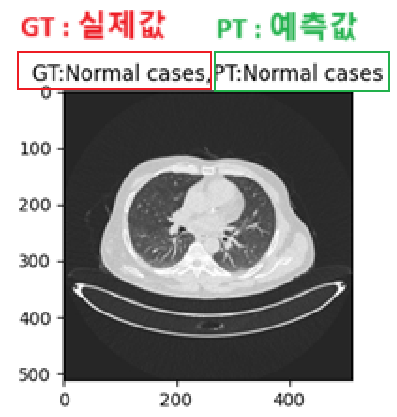

🗒️result가지고 시각화를 했고 이부분은 실제값입니다.

gt = test_file_list[0].split('/')[-2]

gtNormal cases로 확인됩니다.

🗒️예측

#예측

print(torch.argmax(result.probs.data).item())

print(model.names)

pt = model.names[torch.argmax(result.probs.data).item()]

pt2

{0: 'Bengin cases', 1: 'Malignant cases', 2: 'Normal cases'}

Normal cases🗒️시각화

plt.figure(figsize=(3,3))

plt.title(f'GT:{gt},PT:{pt}')

plt.imshow(np.array(img))

plt.show()